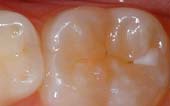

A sealant is a protective coating that is applied to the chewing surfaces (grooves) of the back teeth (premolars and molars), where four out of five cavities in children are found. This sealant acts as a barrier to food, plaque and acid, thus protecting the decay-prone areas of the teeth.

Before

Sealant Applied

After Sealant

Applied